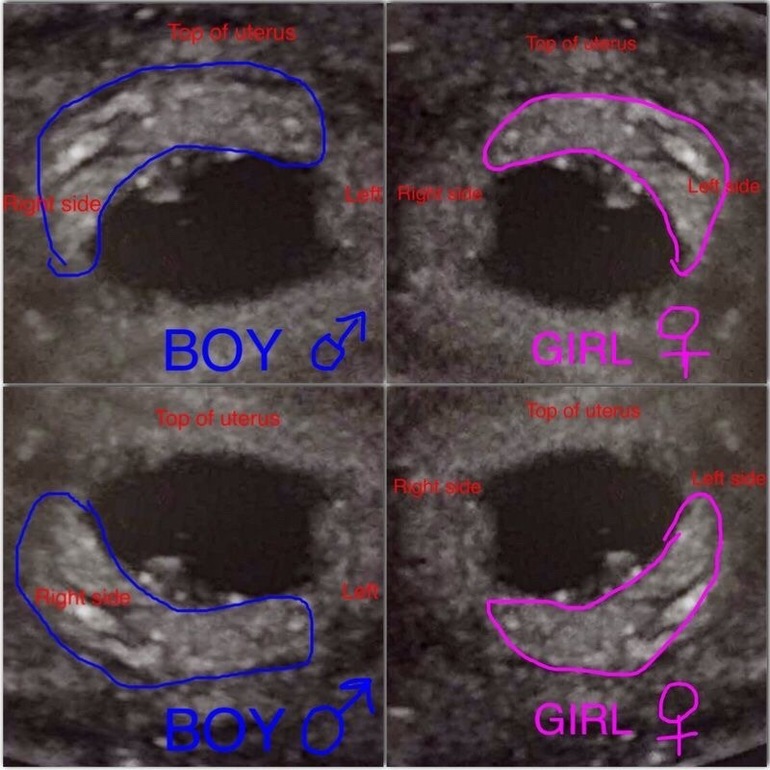

НЕ ПЕРВЫЙ малышВот такую теорию я первый раз встречаю😅 Суть на картинке🤔

Ну вторая теория точно бред) А первая имеет право на существование. Но нужно помнить что на фото могут сделать как зеркальное отображение так и нет. Ну и конечно метод действует на ранних сроках, вроде до 10 недели.

Если УЗИ трансвагианальное, то мальчики слева, потому что там зеркальное отображение. У меня, как не странно, совпало.